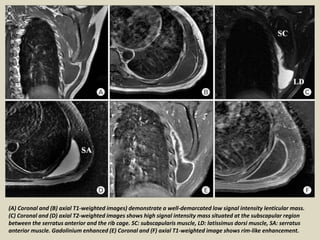

(A) Coronal and (B) axial T1-weighted images) demonstrate a well-demarcated low signal intensity lenticular mass.

(C) Coronal and (D) axial T2-weighted images shows high signal intensity mass situated at the subscapular region

between the serratus anterior and the rib cage. SC: subscapularis muscle, LD: latissimus dorsi muscle, SA: serratus

anterior muscle. Gadolinium enhanced (E) Coronal and (F) axial T1-weighted image shows rim-like enhancement.